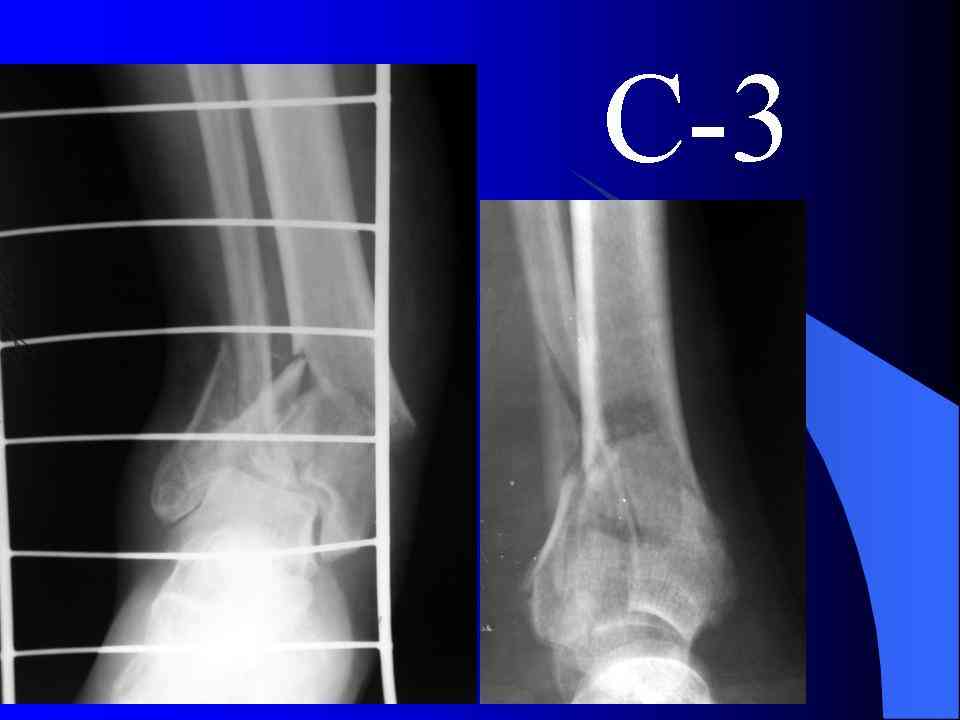

Это типичный перелом пилона, который надп лечить только открыто.Извини те что опоздал к обсуждению, но даже если вы уже оперировали больного по Илизарову это даже лучше.Посылаю картинки.

На рентгенограммах типичный перелом пилона по типу С-3. есть опыт до 100 открытых опреаций у нас в клинике. 20 примерно в год. Принцип один -все внутрисуставные переломы нуждаются в открытой репозиции и внутренней стабильной фиксации. При поступлении КТ не надо, так как получается только нагромождение костей. Истинной картины нет. Главное восстановить длину малоберцовой кости - это ключ к успеху. При поступлении меньше всего надо думать о сосудистых расстройствах, т.к. сама операция и репозиция даже сначала частичная даёт улучшение сосудитых нарушений. Причём очень быстро. Операция в 2этапа. При поступлении доступ позади наружной лодыжки, причём обязательно. После этого репозиция малоберцовой кости и фиксация пластиной 1/3 трубки под винт 3,5. Дренаж и любой аппарат наружной фиксации. Затем после спадения отёка на 5-7-10 день аппрат снимается и дугообразный разрез спереди от медиальной лодыжки 10-12 см. Главной чтобы расстояние между 1 и вторым разрезом было не меньше 7-8 см. Тогда не будет некрозов лоскутов. Таранная кость используется как матрица на неё укладываются отломки и фиксируются пицами. Ренг-контроль. Отломки лежат все отдельно, но ничего не высыпется. При переломах С-3 всегда нужна костная пластика (из крыла). Фиксация пластиной лист клевера простой или LCP. Гипс не нужен. Дренаж до 48 часов. Операция длится 3-4 часа обязательно без жгута. Посылаю примерно такой же случай.

Послала ещё два снимка, если не пройдут, пошлю ещё. Дрягин. Если есть вопросы, готов ответить.